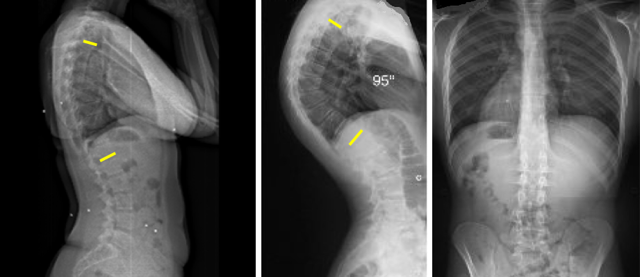

Тщательное обследование поможет установить точный диагноз и подобрать максимально эффективное лечение. После первичного осмотра обязательно назначают рентгенографию или более современные методики – КТ и МРТ.

Эти исследования позволяют выявить патологии позвоночного столба и прилегающих тканей, фиксируя малейшие отклонения от нормы.

На снимках отчетливо просматриваются малейшие изменения как в самом позвоночнике, так и в прилегающих тканях